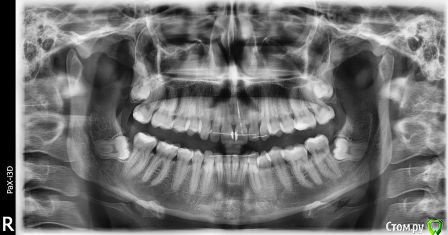

kotik-abarmotik Опубликовано 8 ноября, 2016 Автор Поделиться Опубликовано 8 ноября, 2016 (изменено) [Доброго времени суток ! Как положено прикрепляю фото . Надеюсь мои снимки окажутся информативными. Изменено 8 ноября, 2016 пользователем kotik-abarmotik Ссылка на комментарий

Brigita Опубликовано 9 ноября, 2016 Поделиться Опубликовано 9 ноября, 2016 Судя по снимку этот несчастный кусочек ретейнер наоборот приклеен низко.Варианты могут быть такие1. Повторно брекеты. Справа в боковом отделе нет контактов и кусаете Вы как раз на центральные зубы- вся нагрузка приходится на них. Ретейнер клеить на все поверхности зуба в конце лечения.2 Компромиссный вариант, который решает только вопрос эстетики переднего отдела - капа с перестановкой. На фото плохо видно, но кажется, что зубы "адаптированы" друг к другу по наклону?У вас был дистальный прикус - нижняя челюсть меньше верхней? Ссылка на комментарий

Kazankov.Egor Опубликовано 9 ноября, 2016 Поделиться Опубликовано 9 ноября, 2016 Очень хочется увидеть тот же цикл фотографий, но зубы закройте пожалуйста край в край. Ссылка на комментарий

IvanK Опубликовано 14 ноября, 2016 Поделиться Опубликовано 14 ноября, 2016 думаю, что нужно снова ортодонтическое лечение, удаление 8ок Ссылка на комментарий